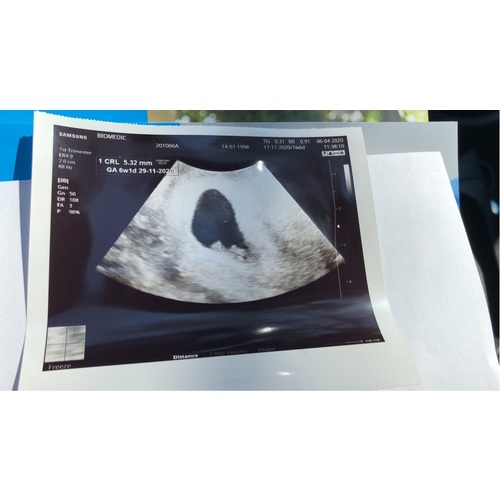

mijn echo met 6.3 weken.. hartje was toen net begonnen met kloppen.. wel inwendig maar voel je weinig van beetje druk in je onderbuik